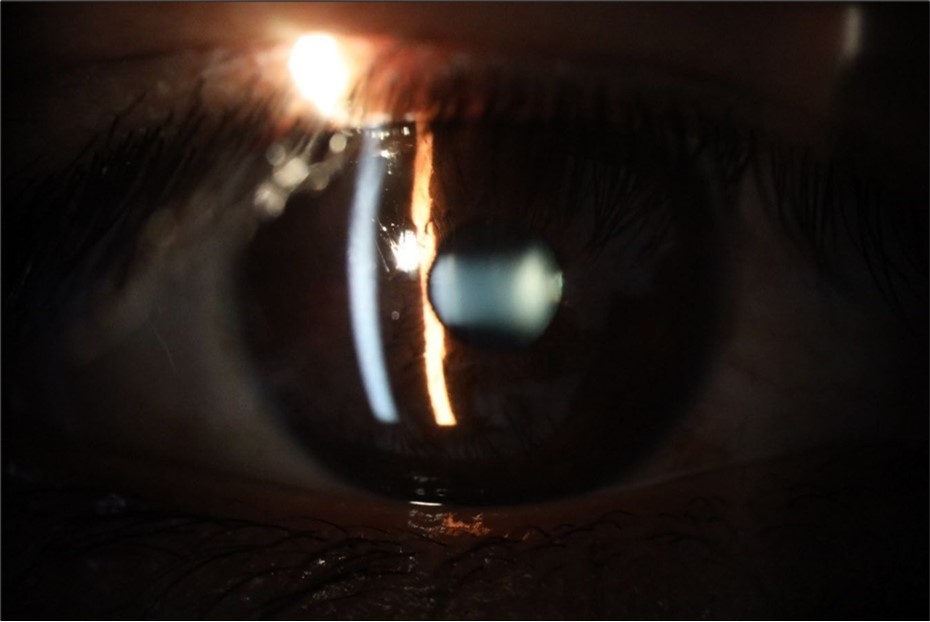

Figure 5.The slit-lamp photograph shows the anterior segment, relatively unscathed, in terms of transparent media (Cornea, crystalline and vitreous).

The slit-lamp photograph shows the anterior segment, relatively unscathed, in terms of transparent media (Cornea, crystalline and vitreous).

Figure 16.The anterior segment of the right eye shows the vitreous with greater transparency. The cornea and lens, as well as the anterior chamber, are in good condition.

The anterior segment of the right eye shows the vitreous with greater transparency. The cornea and lens, as well as the anterior chamber, are in good condition.

Figure 20.The mirror reflection of the affected (right) eye continues to improve.

The mirror reflection of the affected (right) eye continues to improve.

Figure 25.Mirror reflection of the affected eye (right side), with good appearance. This indicates that the transparent media of the eyeball (Cornea, anterior chamber, lens, and vitreous) are in good condition.

Mirror reflection of the affected eye (right side), with good appearance. This indicates that the transparent media of the eyeball (Cornea, anterior chamber, lens, and vitreous) are in good condition.

Figure 26.The macrograph of the anterior segment of the right eye (affected) shows very good transparency of the cornea, anterior chamber, lens, and vitreous.

The macrograph of the anterior segment of the right eye (affected) shows very good transparency of the cornea, anterior chamber, lens, and vitreous.

Figure 32.The macro photograph of the right eye shows us a cornea, anterior camera, and crystalline lens in very good condition.

The macro photograph of the right eye shows us a cornea, anterior camera, and crystalline lens in very good condition.

Figure 35.The anatomy of the anterior segment of the left eye is shown without alterations.

The anatomy of the anterior segment of the left eye is shown without alterations.